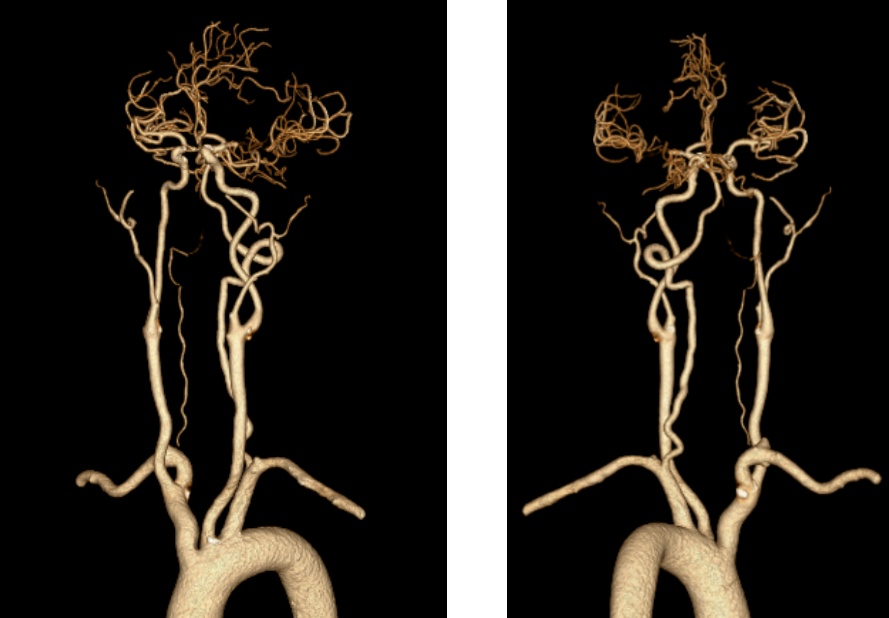

73岁男患,因“右侧肢体无力伴不能言语1小时余”入院;既往有脑梗死病史,未口服脑卒中二级预防药物治疗。入院时心电图提示心房颤动;急诊查颅脑CT排除颅内出血,且左侧大脑中动脉高密度征;急诊查头颈部CTA提示左侧大脑中动脉M1段闭塞,急诊查头颅CTP提示左侧大脑半球低灌注。考虑心源性脑栓塞,急诊行静脉溶栓桥接机械取栓治疗,最终病人恢复正常出院。

术前CTA提示左侧大脑中动脉M1段闭塞

术后复查CTA